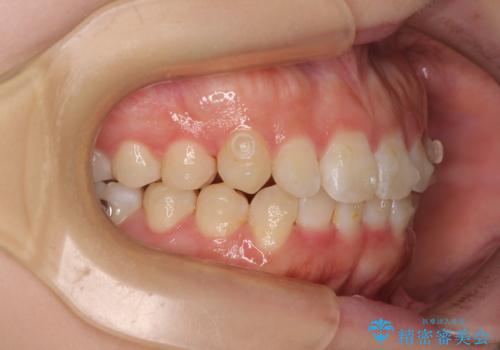

前歯のデコボコを整える インビザラインによる矯正治療

- 上下前歯のデコボコを気にして来院された患者様です。

叢生は軽度であり、ワイヤー矯正でもマウスピース矯正でも対応可能であったので、好きな装置を選んでもらいました。

相談の結果、インビザラインによる矯正治療を行うこととしました。

毎日の装着時間をしっかりと守っていただいたことで、1年程度で無事に治療を終えることができました。